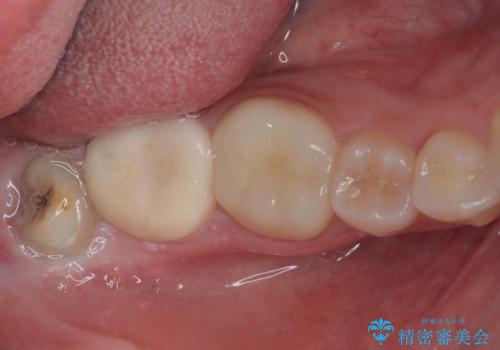

- 親知らずの抜歯希望の患者さまです。

かかりつけの歯科では大学病院への紹介になると言われたが、予約がかなり先になってしまうため、早期の抜歯を希望して来院されました。

CTで神経の走行位置を確認し、抜歯術を行いました。

親知らずは生え方によっては磨きにくく、虫歯や親知らず周囲の歯肉炎による腫れや痛みを引き起こすため、抜歯をお勧めする場合があります。